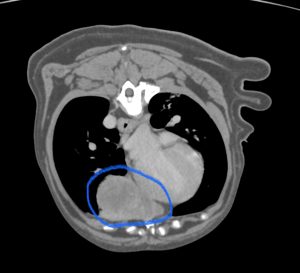

こんにちは。獣医師の永井です。 今回は肺葉捻転についてです。 犬猫の肺はバナナの房のように前葉、中葉、後葉(副…]]>

こんにちは。獣医師の永井です。 今回は肺葉捻転についてです。 犬猫の肺はバナナの房のように前葉、中葉、後葉(副…]]>